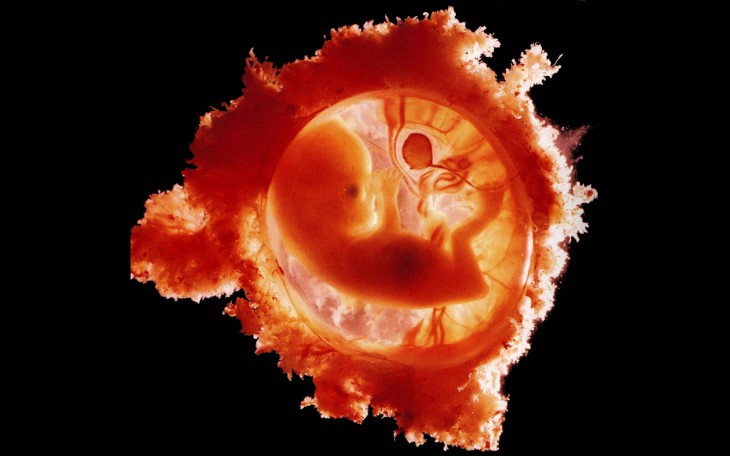

Постепенно прикрепленная к стенке матки оплодотворенная яйцеклетка будет расти и развиваться, превращаясь в эмбрион, который приобретет характерную форму, напоминающую букву С. У плода начнут формироваться ручки и ножки.

- Имеет круглую или овальную форму.

- Отличается небольшими размерами.

- Содержит желточный мешочек.